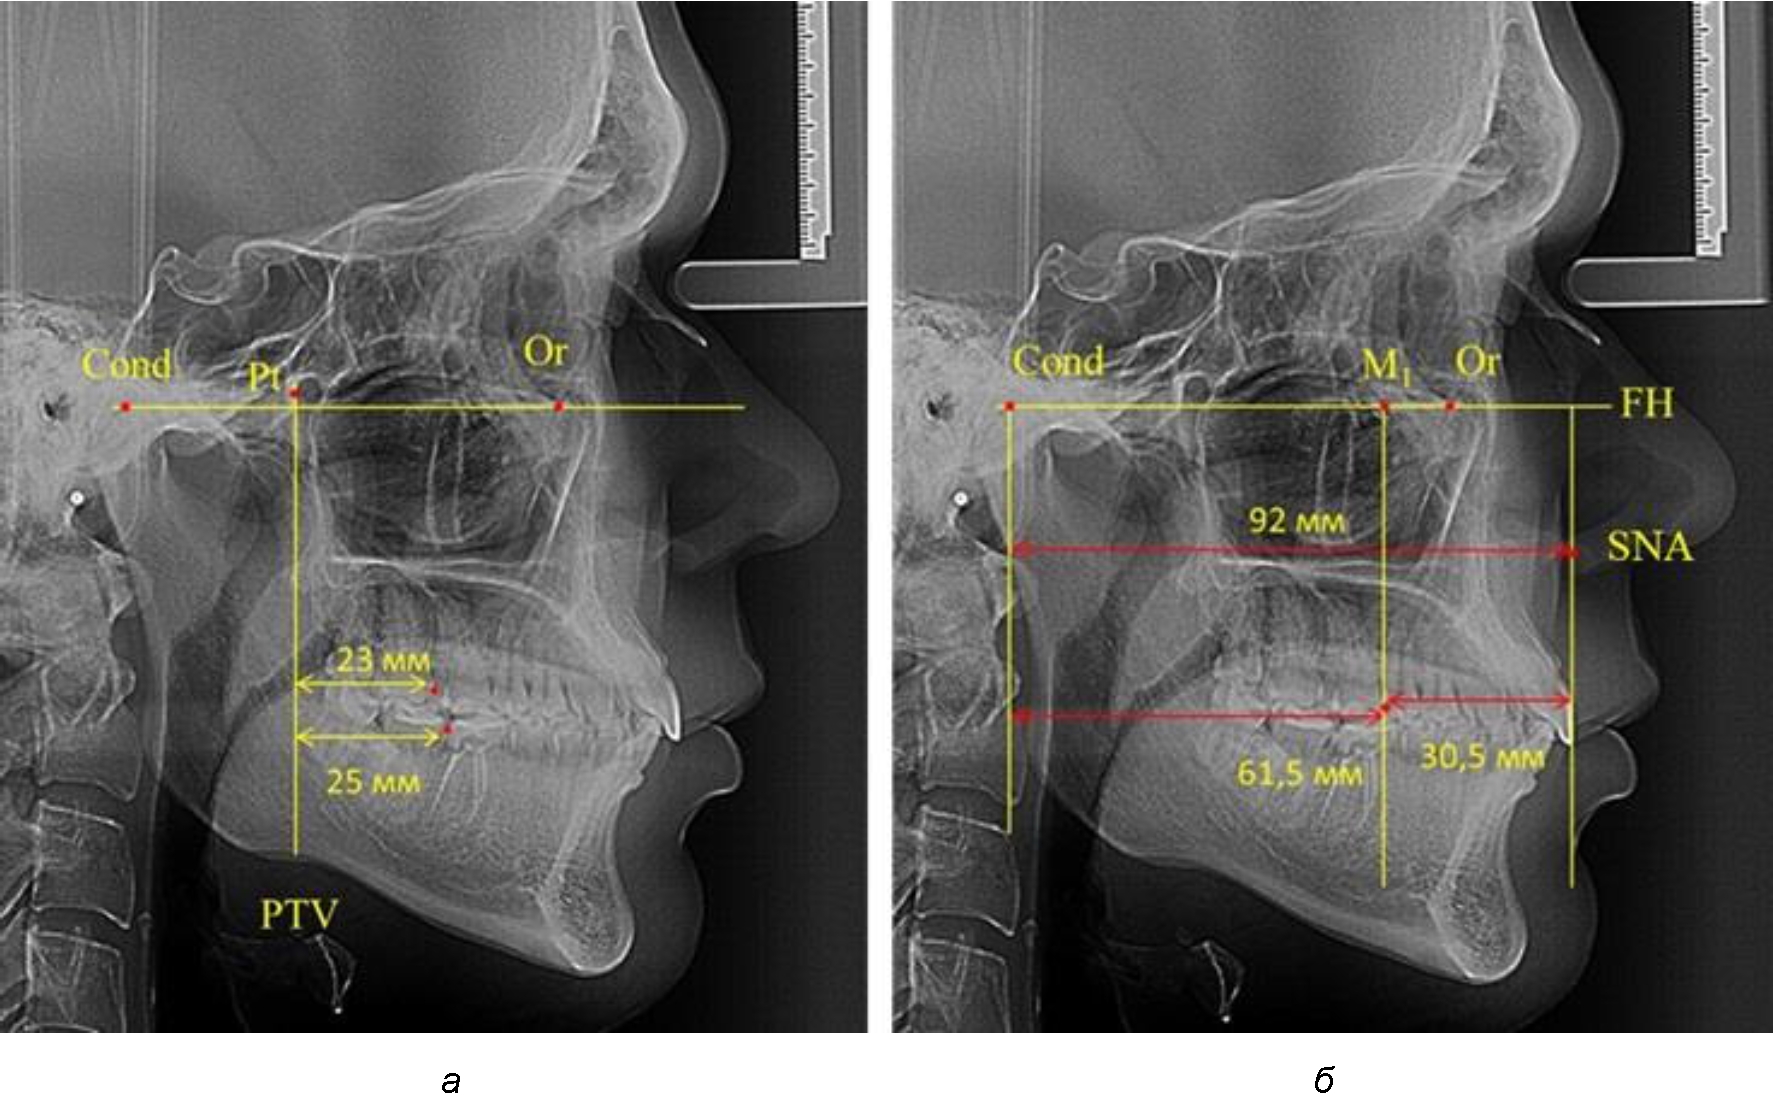

Рис. 1. Метод определения положения первых верхних моляров по Ralph E. McDonald (а) и по предложенному методу (б)

При проведении анализа к Франкфуртской горизонтали проводили передний и задний перпендикуляры. Передний спинальный перпендикуляр проходил через выступающую точку передней носовой ости (spina nasalis anterior – SNA), а задний суставной перпендикуляр опускали из кондилярной точки Cond. Молярный перпендикуляр проводили через медиальную поверхность первого постоянного моляра. Указанная вертикаль отделяла замещающие зубы постоянного прикуса от добавочных зубов (постоянных моляров), что вполне логично для анализа положения первых постоянных моляров в гнатическом комплексе (рис. 1).

Находили положение точки Pt, которая располагалась на пересечении нижнего края круглого отверстия и задней стенки крыловидно-верхнечелюстной щели, и перпендикулярно к Франкфуртской горизонтали проводили крыловидную вертикальную линию, которую принято обозначать как плоскость PTV. Расстояние от крыловидной вертикальной плоскости PTV до дистальной поверхности верхнего первого постоянного моляра определяло его положение, которое, по мнению R. E. McDonald, соответствовало возрасту пациента, увеличенному на 3 мм.

Согласно указанному методу на рентгенограммах проводили Франкфуртскую горизонталь. Учитывая мнения специалистов относительно ориентиров для построения и вариабельность положения наружного слухового прохода, в качестве задней точки использовали верхнюю выпуклость суставной головки нижней челюсти («Cond»). Передняя точка традиционно располагалась на нижнем крае глазницы и определялась как орбитальная точка Or.

Если метод R. E. McDonald позволял оценить только положение первых постоянных верхних моляров, то предложенный метод учитывал сагиттальные индивидуальные размеры гнатического отдела лица и определять соотношение межу его размерами в передней и задней части.